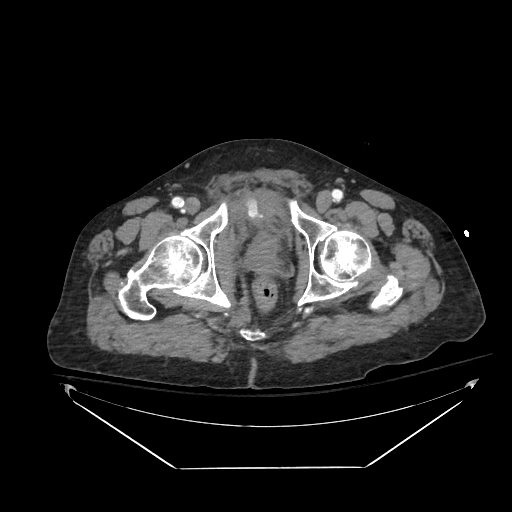

The day continued with a post renal biopsy bleed with active extravasation and a pseudoaneurysm, both of which were easily addressed with LAVA-18. Both patients are doing well after successful procedures. @SirtexMedical @thegestgroup

First day with LAVA-18 and it was quite the day. Our first case was a hypotensive patient with a pelvic fracture and active bleeding (with the LAVA coming off the delivery truck right to the angio suite and right into the patient). @SirtexMedical @thegestgroup